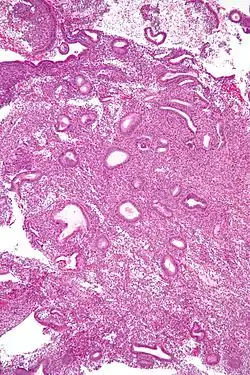

Hyperplasie de l'endomètre

L'hyperplasie endométriale est une prolifération bénigne de l'endomètre dans l'utérus. L'hyperplasie endométriale est classée en fonction de sa cytologie et du tissu glandulaire. Elle peut être simple, complexe et atypique, avec un risque croissant d'évolution vers un cancer de l'endomètre.